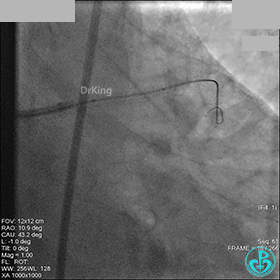

1周后再次上台,右冠脉3级血流,3段局限性严重狭窄,内膜模糊,应该是上次操作夹层遗留下的血肿。

先处理前降支开口严重狭窄并顺利植入前降支到左主干支架。